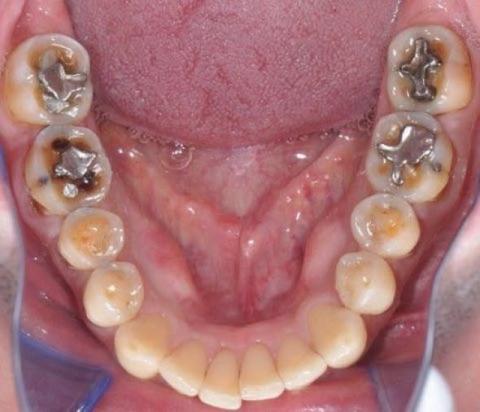

Upon close examination of the lower arch, multiple amalgam restorations are evident, particularly on the molars and premolars. Despite long-term exposure to severe bruxism (teeth grinding), these amalgam fillings remain intact — a testament to their durability. However, adjacent enamel wear, minor fractures, and surface abrasions indicate progressive occlusal stress and potential loss of tooth structure over time.

Heavy wear on occlusal surfaces (molars and premolars).

Amalgam restorations still functional but surrounded by enamel microcracks.

Signs of enamel thinning, flattening, and dentin exposure due to chronic grinding.

Chronic Bruxism (Severe Grinding)

Occlusal trauma with secondary enamel wear

Functional amalgam fillings but possible microleakage risks

Potential gum recession due to constant pressure